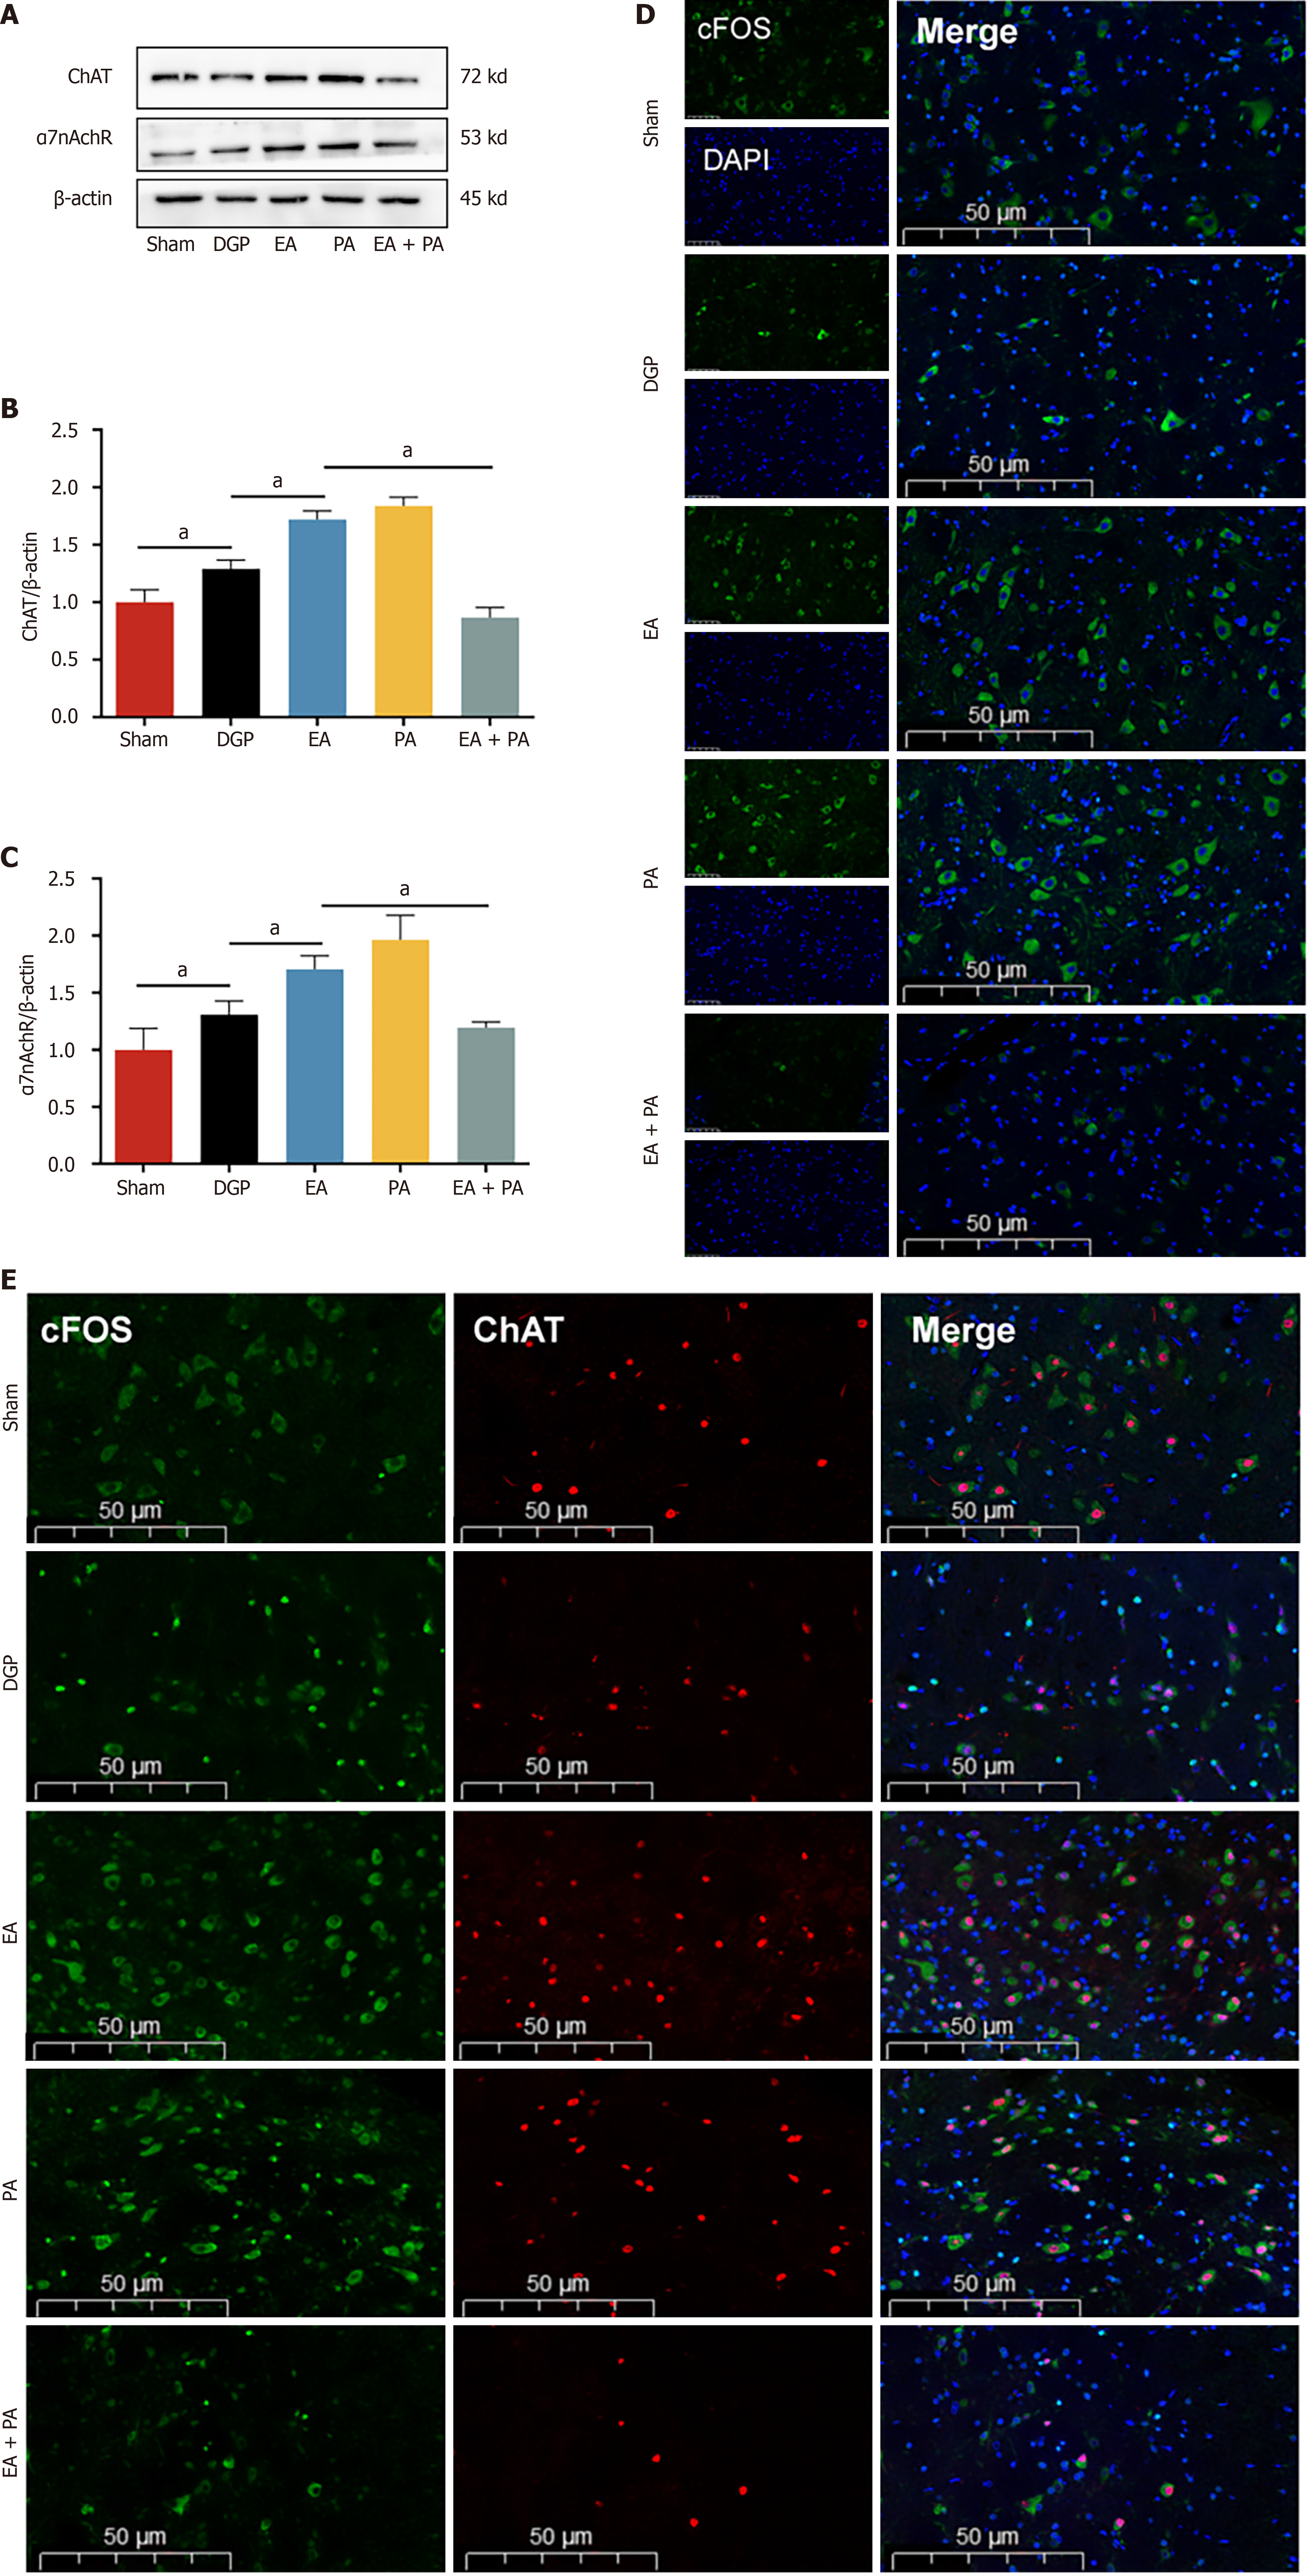

In order to elucidate the afferent neural pathways underlying EA-mediated gastric motility modulation in DGP rats, the ChAT inhibitor AP or the agonist PA was injected into the ST36 acupoint area and ChAT and α7nAChR protein expression was quantified across three key sites (Figures 4, 5 and 6): The ST36 acupoint skin, the spinal L4-L6 segments and the NTS (Figures 4A, 5A and 6A). Western blot analysis revealed significantly elevated ChAT levels in DGP rats compared to Sham controls across all sites (P < 0.05), with EA further amplifying ChAT expression (P < 0.05), mirroring trends observed in the PA group. However, the co-administration of AP with EA (EA + AP group) led to the abolition of this activation (P < 0.05; Figures 4B, 5B and 6B). In addition, EA induced an increase in α7nAChR expression in the ST36 skin, L4-L6 spinal region, and NTS (P < 0.05), an effect that was attenuated by AP co-treatment (P < 0.05; Figures 4C, 5C and 6C). Immunofluorescence analysis corroborated these observations. DGP rats exhibited reduced ChAT expression in ST36 skin, whereas EA and PA groups showed marked increases. AP administration nullified EA’s effects (Figure 4D). In the spinal L4-L6 segments, c-FOS immunostaining revealed robust neuronal activation in the EA and PA groups (P < 0.05), which was suppressed in the EA + AP rats (P < 0.05; Figure 5D). c-FOS +/ChAT + co-localization further confirmed that this activation was ChAT-dependent (Figure 5E). In the NTS, c-FOS expression was significantly elevated in the EA and PA groups (P < 0.05), with EA + AP rats showing reduced activation (P < 0.05; Figure 6D). c-FOS +/ChAT + co-expression mirrored these trends, demonstrating EA’s dual modulation of neuronal activity and cholinergic signalling (Figure 6E). The data taken together indicate that EA activates vagal ChAT/α7nAChR targets at ST36, transmitting signals via spinal L4-L6 afferents to NTS neurons, thereby restoring vagal tone in DGP.